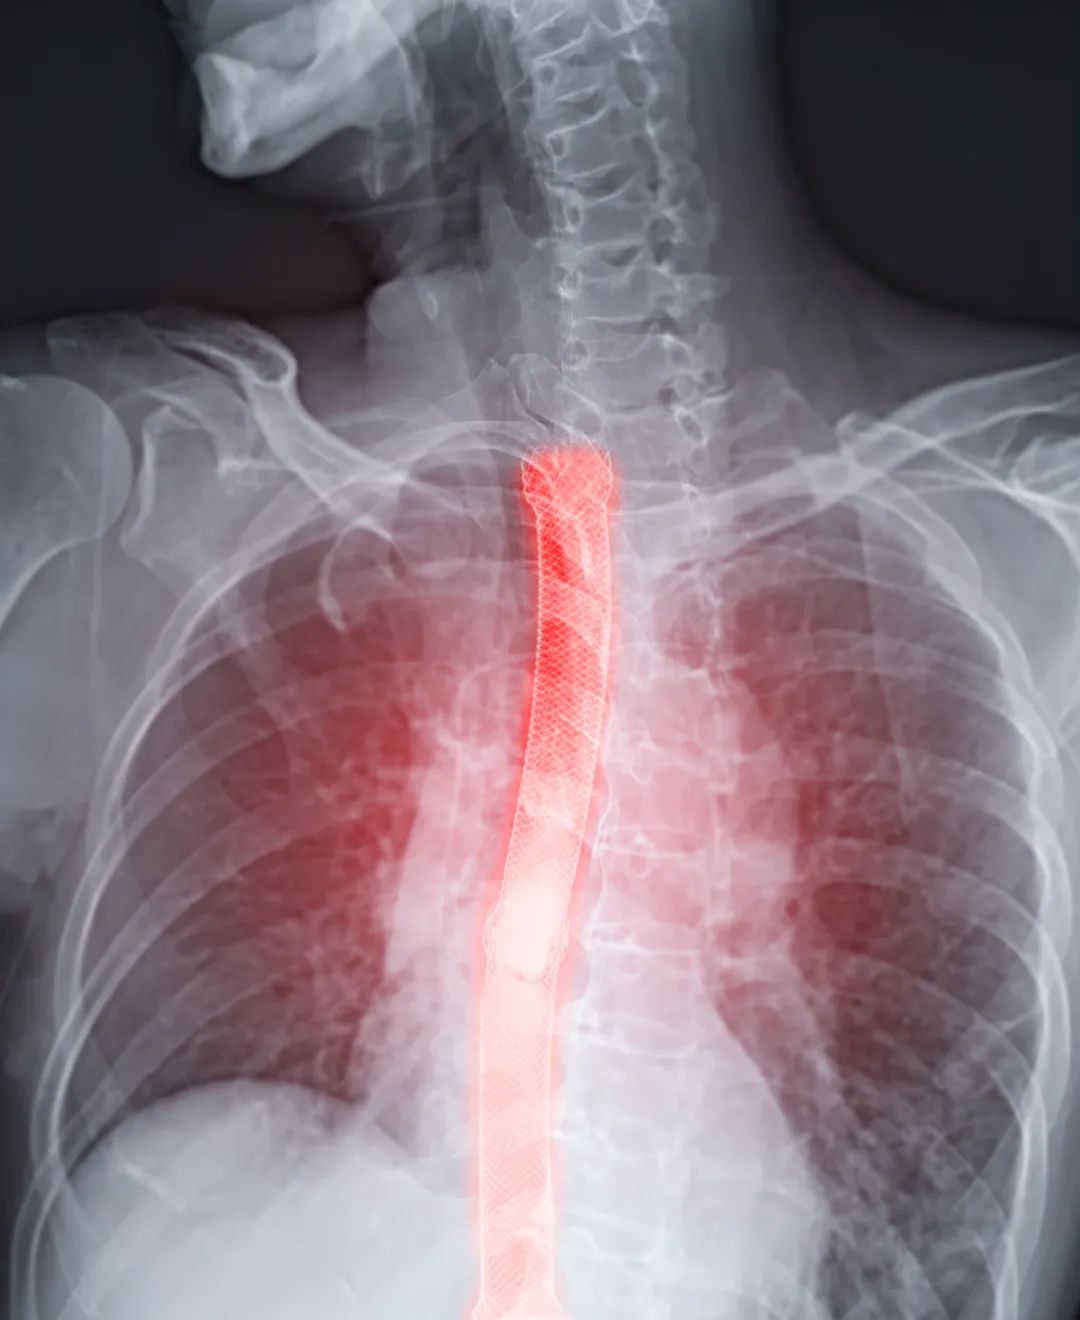

食管可是真正处在“咽喉要道”的